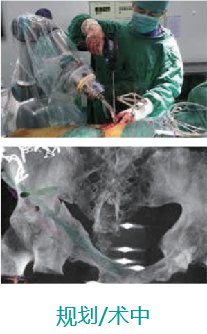

天玑II创伤手术—骨盆手术

天玑II 辅助骨盆髋臼骨折内牢靠术

基本情形:患者男,,,,,,,,69岁,,,,,,,,骨盆左侧髋臼前后柱损伤

机械人辅助优势:天玑II机械臂最后控制快速选择和执行手术妄想,,,,,,,,通道螺钉精准定位,,,,,,,,镌汰术中透视。。。。。。。

病例泉源:北京积水潭医院